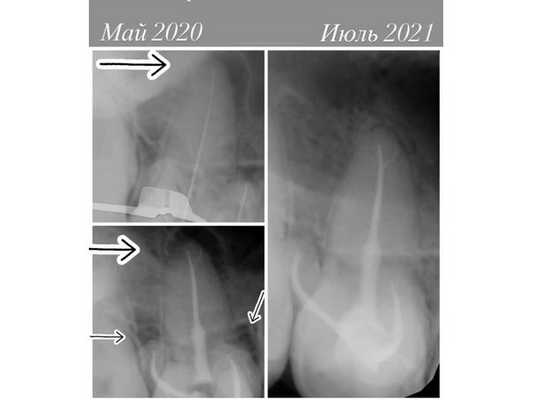

В мае 2020 года в стоматологическую клинику обратился 25-летний мужчина с жалобой на дискомфорт в области правого верхнего моляра (1.6).

Осмотр поражённого зуба выявил кариес и несостоятельную пломбу, край которой прилегал неправильно. Прощупывание слизистой оболочки в области верхушки корня, как и зондирование зуба, безболезненно, простукивание моляра слабо болезненное.

Реакции на холод не было. При электроодонтодиагностике (ЭОД) зуб реагировал на ток выше 100 мкА, что говорит о возможном периодонтите.

- сделали рентген-снимок, который показал, что корневые каналы запломбированы однородно до физиологической верхушки;

В июле 2021 года рентген показал, что разрушение костной ткани у верхушек корней зуба 1.6 уменьшилось. Мужчина отметил, что чувствует себя хорошо, боль прошла. Корневые каналы были качественно закупорены, анатомическая форма и функции зуба восстановлены.